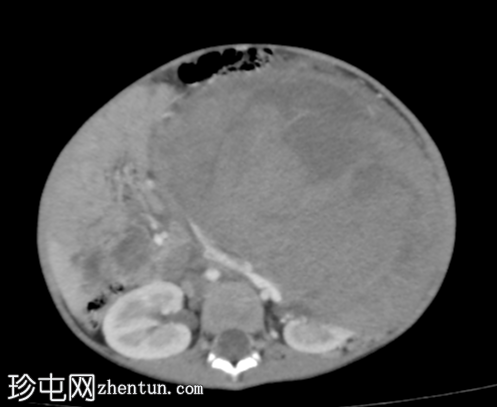

CT

轴位增强扫描(门静脉期)

CT扫描显示左侧腹盆腔内存在一个较大的、部分边界清晰、呈不均匀强化的软组织密度肿块。肿块后方与左肾无法分离。

肿块对邻近器官有明显的压迫作用。

右肾外观未见异常。